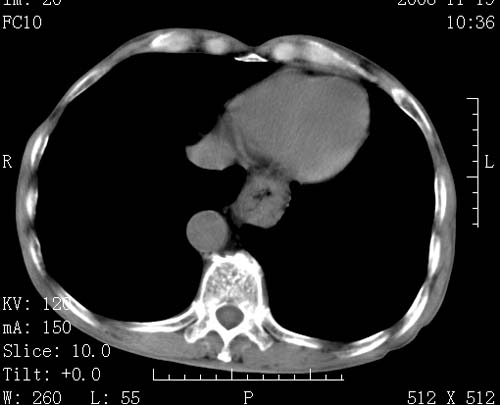

标题: CT16691:m 67 胃镜确诊食管下段及贲门癌 [打印本页]

标题: CT16691:m 67 胃镜确诊食管下段及贲门癌

术前查体,双肺部结节是转移?结核?请点评

1)符合食管癌表现。2)两肺及纵隔淋巴结多发性转移瘤。3)左肺上叶舌段及两肺下叶炎症感染。

1)符合食管癌表现。2)两肺及纵隔淋巴结多发性转移瘤。3)左肺上叶舌段支气管扩张伴感染.

食管癌伴双肺转移,评述:肺部毛细血管网丰富,全身血液均快速流经肺部,癌细胞容易过滤定植,形成转移瘤,影象特点为以毛细血管末梢为中心的结节灶,边缘光滑锐利,少见有中心空洞着,不同来源的转移瘤可有各自特点,如甲状腺癌为双肺弥漫性微结节,本例有原发灶,双肺影象灶典型,左肺舌段条带状网格样伴胸膜天幕征,可视为癌性淋巴管炎。

左肺舌段有斑点钙化灶,能否说明是结核而不是转移?如果是转移将放弃手术改成化疗,如果是结核将考虑择期手术